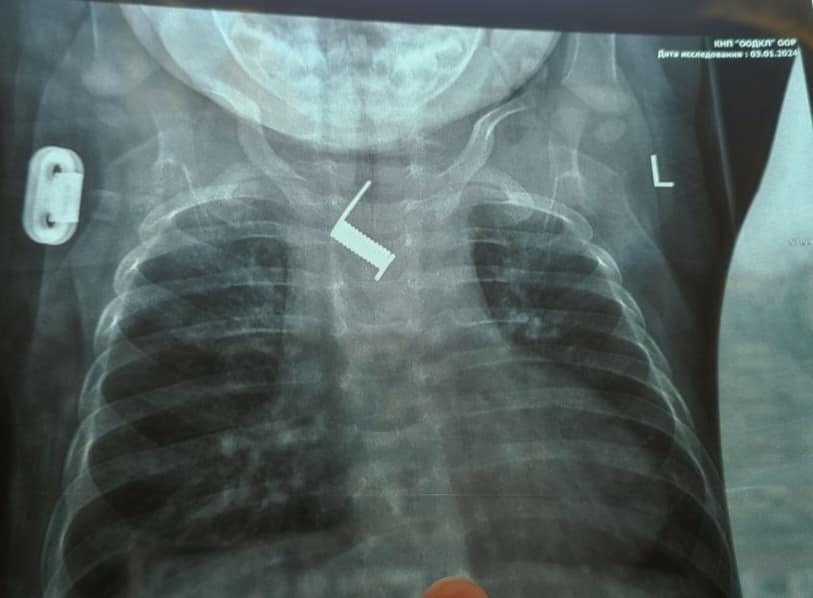

Лікарі, зробивши рентген, виявили наявність стороннього тіла у стравоході.

Стороннє тіло виявилося пружиною від шпильки для волосся, яка практично вросла у стравохід дитини.

“Знаходилось стороннє тіло на рівні середньої третини стравоходу, поряд з дугою аорти. Стороннє тіло було видалено ендоскопічно, що позбавило дитину від важкого хірургічного втручання та ризиків для життя”, — йдеться у повідомленні.